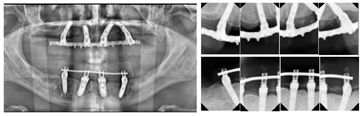

患者口腔卫生差,恒牙列,11、17、26、27、36、41、46、47缺失,11、41见树脂牙修复,牙冠形态不规则,11与21、22、23、12、13间,41与42、43、31、32间可见树脂与金属结扎丝连接固定,树脂连接体部分折裂,边缘见明显悬突。上下颌余留牙齿舌侧见大量牙石,全口牙龈萎缩,牙根暴露约1/3,牙龈局部红肿明显,探诊出血。全口余留牙齿松动Ⅲ度。口腔黏膜检查未见明显异常(图1)。